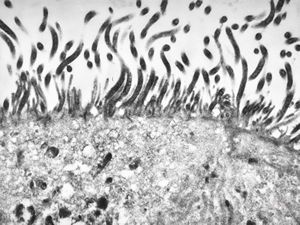

F,52y. | spirochetosis - colon